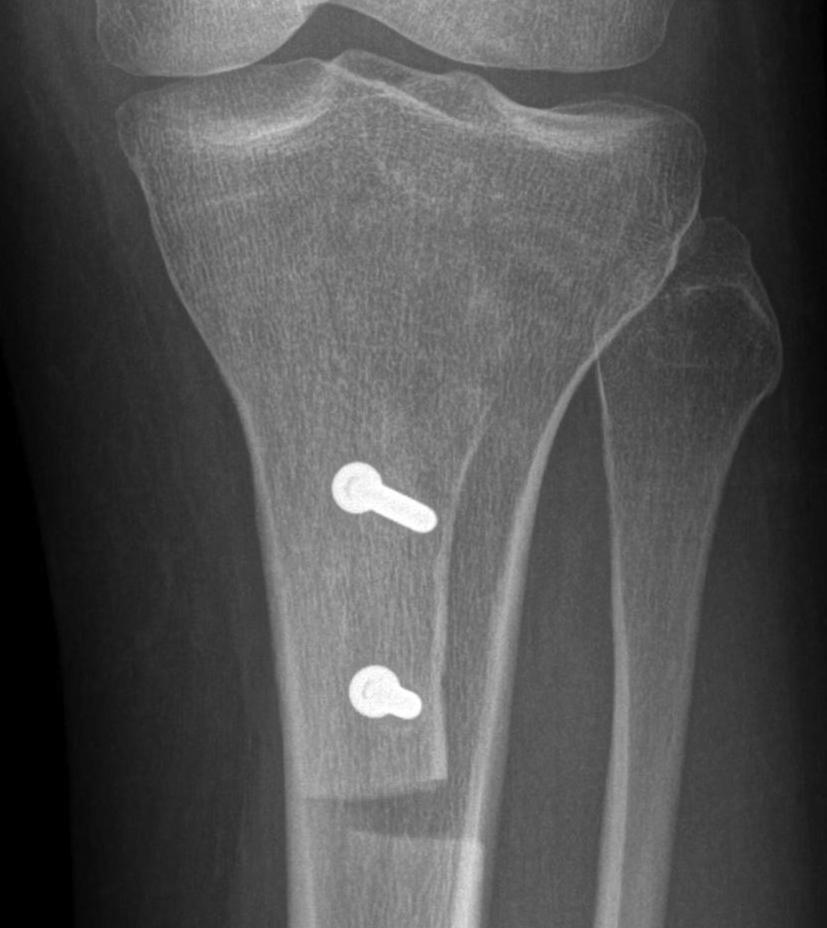

Tibial tuberosity osteotomy

Types

Maquet - elevation

Elmslie-Trillat - medialization

Fulkerson - anteromedialization

Maquet procedure

Technique

Perform TTO then elevate with insertion bone graft

- originally described elevating by 2.5 cm

- problems with skin necrosis / prominence

- reduced to only 1 cm and recommended via an anterolateral incision